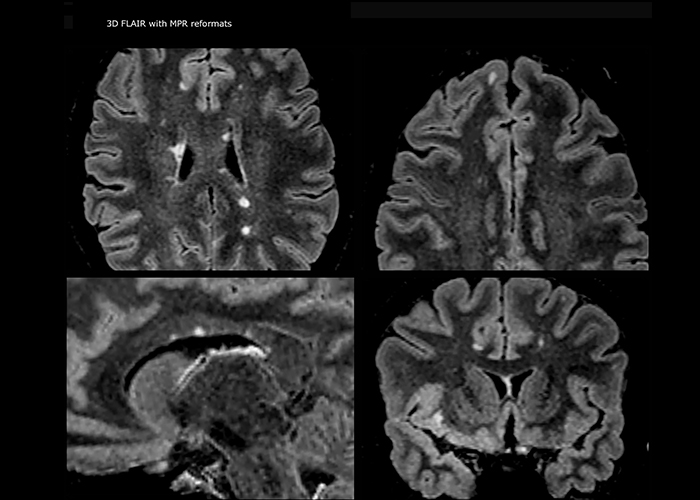

Multiple sclerosis imaging requires precision, speed

When multiple sclerosis (MS) is suspected, clinicians need a diagnosis early on, so treatment can begin as soon as possible. “A challenge for imaging is that MS lesions in the brain and spine may be very small,” says Dr. Savatovsky. “We need precise imaging to tell exactly where the lesion is, so we need high quality, very high resolution images, preferably in 3D[1]. We need to know if a high T2 signal intensity is suggestive of MS or just aspecific. And we want to visualize active lesions very well.”

Imaging MS in brain

For MS imaging in the brain, Dr. Savatovsky uses 3D FLAIR as the basic sequence to visualize the lesions and assess the situation and lesion load. “We count the lesions in each location to determine if the criteria of the disease are fulfilled. We use a T2-weighted sequence because our neurologists are used to it. We compare the lesion load on FLAIR with a 3D T1 post-contrast sequence to help us determine whether lesions are old or new. We typically administer the contrast before the patient enters the machine because it shortens the examination time and allows to visualize active lesions that tend to be more visible after several minutes. When a differential diagnosis is difficult, we add sequences such as susceptibility imaging, because some focal MS lesions have a small vein in the center[3].”